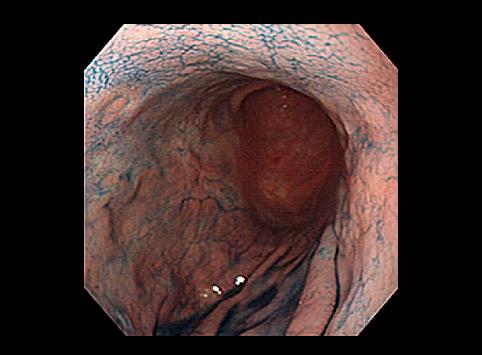

疾病(病理主体)的分类恶性上皮性肿瘤/腺癌

部位(按器官分)胃(部位)/2个以上

肿瘤的肉眼分类0型(表在型)/IIb型(IIb+IIc)

肿瘤最大直径40以上

肿瘤的深度m